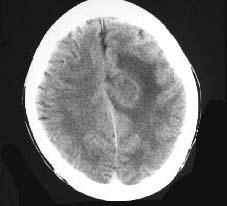

成年男性,头疼、头胀、发热,血象高,CT检查如图,选择最可能的诊断()A.脑脓肿B.胶质瘤C.皮样囊肿D.脑梗死E.脑膜瘤

问题 成年男性,头疼、头胀、发热,血象高,CT检查如图,选择最可能的诊断()

选项 A.脑脓肿 B.胶质瘤 C.皮样囊肿 D.脑梗死 E.脑膜瘤

答案 A